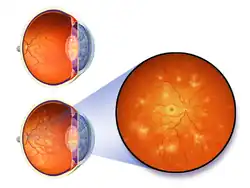

The eyes may show bleeding in the retina, an exudate, cotton-wool spots, scattered splinter hemorrhages, or swelling of the optic disc called papilledema.